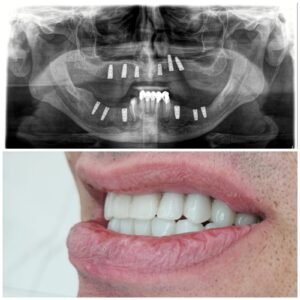

تقنيات حديثة للزراعة

تضيف اجهزه البانوراما الداخلية واجهزة التصوير ثلاثية الأبعاد بعدًا آخر لتقنية الزرع من خلال صورها الدقيقة للفك والأسنان. هذه الدقة ضرورية لتخطيط ووضع الغرسات. يوفر تقييمًا دقيقًا للبنى التشريحيه مثل الأعصاب وجذور الأسنان والجيوب الفكية ومعرفة طبيعة العظم وكثافة وما إلى ذلك ، مما يمنع أي احتمال للفشل الذي يحدث بسبب التشخيص الخاطئ. تم تجهيز مراكز الزرع لدينا بهذه الآلات المتطورة ، مما يمكننا من تنفيذ كل حالة من حالات الزرع بدقه عاليه وأعلى درجات النجاح.